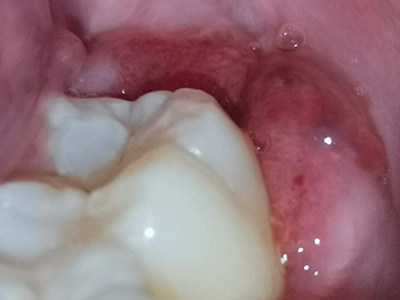

智齿冠周炎右下方智齿牙龈处有小疙瘩图

智齿冠周炎患者口腔右下方智齿的牙龈处有一小疙瘩,小疙瘩表面红肿,边缘微微发白,可见少量的牙齿萌出,周围黏膜有明显的充血、发红样。